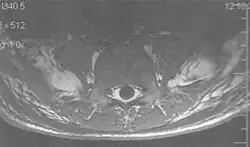

A wrap-around artifact also known as an aliasing artifact, is a result of mismapping of anatomy that lies outside the field of view but within the slice volume.[4] The selected field of view is smaller than the size of the imaged object. The anatomy is usually displaced to the opposite side of the image (Figs 6 and 7). It can be caused by non-linear gradients or by undersampling of the frequencies contained within the return signal.[1] The sampling rate must be twice the maximal frequency that occurs in the object (Nyquist sampling limit). If not, the Fourier transform will assign very low values to the frequency signals greater than the Nyquist limit. These frequencies will then ‘wrap around’ to the opposite side of the image, masquerading as low-frequency signals. In the frequency encode direction a filter can be applied to the acquired signal to eliminate frequencies greater than the Nyquist frequency. In the phase encode direction, artifacts can be reduced by an increasing number of phase encode steps (increased image time). For correction, a larger field of view may be chosen.[1]